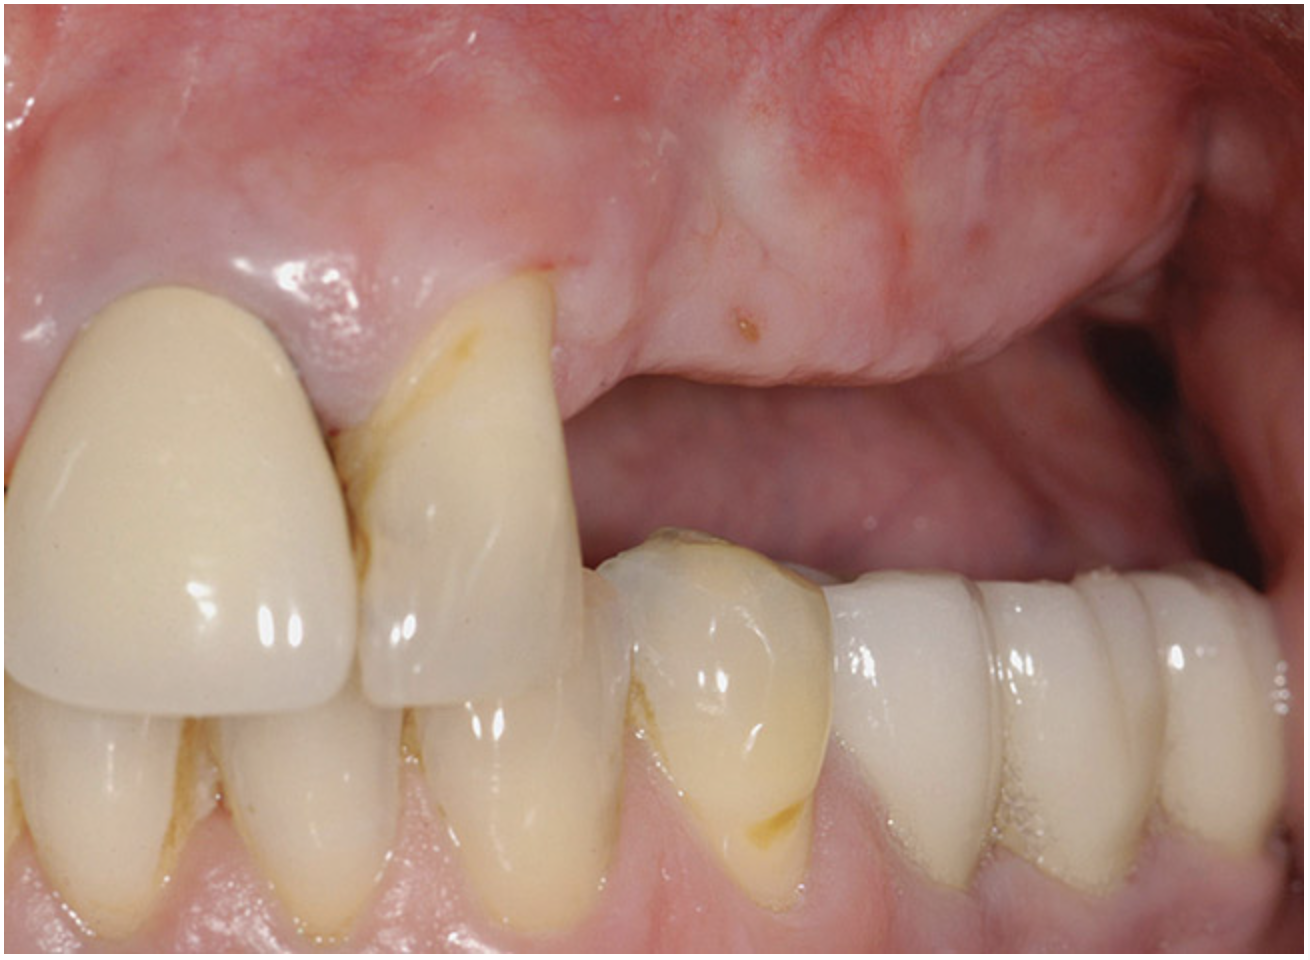

A 62-year-old woman was referred for fixed tooth replacement of the missing maxillary left cuspid, bicuspids, and first molar (Figure 11). Clinical and CBCT evaluation revealed an almost fully pneumatized maxillary left sinus along with alveolar width deficiency. The treatment plan called for a four-unit, implant-supported splinted fixed bridge. A left sinus augmentation along with a ridge split and interpositional bone graft consisting of rhBMP-2/ACS (INFUSE Bone Graft) and mineralized allograft (MinerOss) covered by a dense porous polyethylene mesh (Medpor®, Stryker, www.stryker.com) were done simultaneously (Figure 12, Figure 13 and Figure 14). Six months later, a follow-up CBCT revealed a well-incorporated graft with adequate bone volume and density for implant placement (Figure 15 and Figure 16). Final bridge fabrication followed 3 months later (Figure 17 and Figure 18).

Figure 18  Three months after implant placement, but before soft-tissue vestibuloplasty.

Figure 18